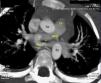

El electrocardiograma y la radiografía simple de tórax fueron normales. En la ecocardiografía transtorácica (Philips En-Visor®) no se detecta cardiopatía cardiaca estructural, pero no se observa la bifurcación del tronco pulmonar, falta el origen normal de la arteria pulmonar izquierda que nace más distal, en la arteria pulmonar derecha, con un trayecto hacia la izquierda y pasa por detrás de la tráquea, creando un anillo vascular con aceleración del flujo sanguíneo a dicho nivel (velocidad pico 1,8m/s), el Doppler color facilita la identificación de la arteria pulmonar anómala (fig. 1).

En el estudio mediante TC multidetector (Toshiba Aquilion, 64 detectores®) se confirmó el diagnóstico de sling de la arteria (fig. 2). La reconstrucción 3D permitió una mejor identificación de la relación espacial entre las ramas pulmonares, aorta, vena cava superior y vena innominada; así como el anillo vascular con el trayecto estenótico de la rama pulmonar izquierda (fig. 3).